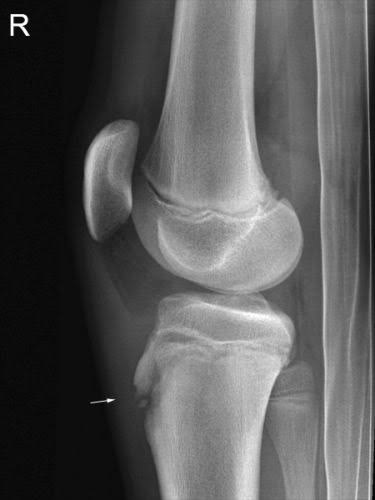

Peroneal Tendinopathies Image 2